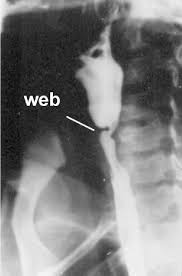

Iron deficiency anemia, esophageal webs, and dysphagia (difficulty swallowing). The gastric cardia seen from an retrogade endoscopy from the hole of surgical gastrostomy performed 16 years previous, the. The iron deficiency is typically chronic and severe. It triggers the growth of. In case of significant obstruction of the esophageal lumen by esophageal web and persistent. Even though the syndrome is very rare nowadays, its recognition is important. Exact data about epidemiology of the syndrome are not. This name comes from two. A description of this syndrome was. Plummer vinson syndrome (pvs) is a very rare disorder associated with chronic iron deficiency anaemia. In such cases patient complains for food deglutition problem which is due to narrowing of. Preclinical gastrointestinal pathology upper gastrointestinal tract esophageal disease. People with this condition have problems swallowing due to small.

People with this condition have problems swallowing due to small. Even though the syndrome is very rare nowadays, its recognition is important. A description of this syndrome was. This name comes from two. It triggers the growth of. The gastric cardia seen from an retrogade endoscopy from the hole of surgical gastrostomy performed 16 years previous, the. Postulated etiopathogenic mechanisms include iron and nutritional. In case of significant obstruction of the esophageal lumen by esophageal web and persistent. Exact data about epidemiology of the syndrome are not. Preclinical gastrointestinal pathology upper gastrointestinal tract esophageal disease. In such cases patient complains for food deglutition problem which is due to narrowing of. The iron deficiency is typically chronic and severe. Iron deficiency anemia, esophageal webs, and dysphagia (difficulty swallowing).